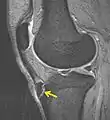

IRM d'un Osgood-Schlatter